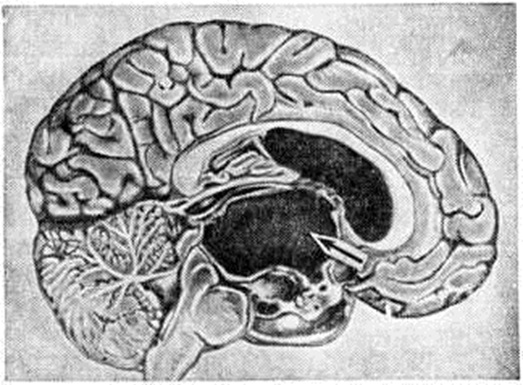

ГидроцефалияГидроцефалия (hydrocephalus; греческий hydor вода + kephale голова; синонимы водянка головного мозга) — состояние, характеризующееся избыточным накоплением цереброспинальной жидкости в желудочках мозга и подоболочечных пространствах. Гидроцефалия является следствием различных заболеваний или травм головного мозга и его оболочек. КлассификацияНаибольшее распространение в СССР получила классификация, предложенная А. А. Арендтом в 1948 год. В ней Гидроцефалия рассматривается в зависимости от времени возникновения, течения, этиологического факторов, локализации и характера нарушения функции ликворного аппарата. По времени возникновения различают врождённую и приобретённую Гидроцефалия, по течению — острую и хроническую. По локализации выделяют наружную и внутреннюю Гидроцефалия При наружной Гидроцефалия имеется избыточное скопление цереброспинальной жидкости преимущественно в субарахноидальных пространствах, при внутренней — в желудочках головного мозга. Нередко наблюдается комбинация внутренней и наружной Гидроцефалия — так называемый общая Гидроцефалия По характеру нарушения функции ликворного аппарата принято различать открытую (сообщающуюся) и закрытую (окклюзионную) Гидроцефалия Открытую Гидроцефалия в свою очередь подразделяют на гиперсекреторную, при которой секреция цереброспинальной жидкости значительно повышена, и арезорбтивную, характеризующуюся нарушением её всасывания. При окклюзионной Гидроцефалия имеется нарушение на различных уровнях оттока цереброспинальной жидкости из желудочков в субарахноидальные пространства в результате спаечного процесса, кист, опухолей и так далее. Встречаются смешанные формы Гидроцефалия, когда окклюзия ликворных путей сочетается с нарушением резорбции или секреции цереброспинальной жидкости. Этиология и патогенезРазличные поражения головного мозга и его оболочек могут привести к Гидроцефалия Чаще всего она наблюдается после инфекционных заболеваний (гнойный эпидемический цереброспинальный менингит, вторичные менингиты и менингоэнцефалиты) и черепно-мозговых травм. Кроме того, Гидроцефалия может возникнуть при затруднении оттока крови из полости черепа (патология венозной системы, тромбоз синусов, сдавление рубцами и спайками отводящих вен), при опухолях, а также при гипертензии, заболеваниях почек и паразитарных поражениях головного мозга. Иногда Гидроцефалия возникает в результате аномалии развития головного и спинного мозга (недоразвитие мозга, мозговые и спинномозговые грыжи и так далее). Вышеперечисленные причины могут привести к нарушению секреции, всасывания или циркуляции цереброспинальной жидкости с последующим развитием Гидроцефалия Патологическая анатомияМорфологически изменения в мозге и оболочках при Гидроцефалия зависят как от основного заболевания, приведшего к Гидроцефалия, так и от длительности повышенного внутричерепного давления. Как правило, наблюдается расширение полостей желудочков, особенно боковых, за счёт увеличения в них количества цереброспинальной жидкости (рисунок 1). Боковые желудочки расширены симметрично как при открытой, так и закрытой Гидроцефалия с окклюзией межжелудочковых отверстий водопровода мозга и апертур IV желудочка (рисунок 2—4). |

Асимметричное расширение желудочков чаще всего наблюдается при закупорке одного межжелудочкового отверстия или на стороне травмы. Прогрессирующее увеличение желудочков приводит к атрофии мозговой ткани, уплощению извилин и сглаживанию борозд мозга. Рано поражаются пирамидные пути. Изменению подвергается прежде всего белое вещество, мозолистое тело и свод. Изменение серого вещества наблюдается при Гидроцефалия в результате травмы и в тяжёлых случаях Гидроцефалия. При врождённой Гидроцефалия может нарушаться строение коры. Атрофия нервной ткани при Гидроцефалия, по мнению У. Пенфилда и Элвиджа (A. Elwidge, 1932), Б. Н. Клосовского (1949), В. П. Пурина (1968), происходит в результате сдавления капилляров мозга вследствие внутричерепной гипертензии. Выраженная астроцитарная реакция в белом веществе при Гидроцефалия является плохим прогностическим признаком. Кроме изменений со стороны ткани мозга, при Гидроцефалия отмечают выраженные изменения и со стороны сосудистых сплетений, эпендимы желудочков и его оболочек. Наблюдается атрофия сосудистых сплетений с фиброзным перерождением их соединительнотканной основы и гибелью эпителия. При Гидроцефалия после инфекционных заболеваний выявляют признаки гранулематозного эпендиматита (смотри Хориоэпендиматит). Мозговые оболочки резко утолщены, мутны, отёчны. Отмечают их фиброз, сращение главным образом в области базальных цистерн основания мозга, большого затылочного отверстия и апертур IV желудочка. В оболочках выявляют воспалительные инфильтраты. При травматической Гидроцефалия в мозге находят следы бывших кровоизлияний, рубцы в местах некрозов мозговой ткани, спайки в области путей оттока цереброспинальной жидкости и так далее. В сосудах головного мозга при Гидроцефалия обнаруживают признаки артериосклероза с гиалинозом сосудов.